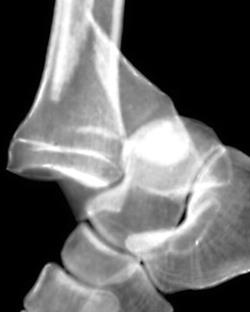

Вывих голеностопного сустава

Вывих голеностопного сустава – это патологическое состояние, при котором наблюдается полное смещение суставных поверхностей костей, образующих голеностопный сустав. Полный вывих голеностопного сустава встречается редко и обычно наблюдается в сочетании с переломом лодыжек. В быту вывихом часто называют растяжения, надрывы и разрывы связок голеностопного сустава, при которых может наблюдаться подвывих – частичное смещение суставных поверхностей. Вывих и подвывих сопровождаются болью, отеком, нарушением движений и опоры. Диагноз устанавливается с учетом данных осмотра и рентгенографии. Иногда дополнительно назначается КТ или МРТ. Лечение подвывихов консервативное. При полном вывихе производится попытка закрытого вправления, при невозможности сопоставить суставные поверхности и отломки костей выполняется операция.

Вывих голеностопного сустава – смещение суставных поверхностей большеберцовой, таранной и малоберцовой костей относительно друг друга. Полные вывихи голеностопного сустава наблюдаются редко, являются тяжелой травмой, сочетаются с внутрисуставными и околосуставными переломами.

Голеностопный сустав – сложный блоковидный сустав, образованный тремя костями: таранной, малоберцовой и большеберцовой. Нижняя поверхность эпифиза большеберцовой кости прилежит к верхней части таранной кости. Наружная лодыжка, являющаяся продолжением малоберцовой кости, а также внутренняя лодыжка, образованная дистальной частью большеберцовой кости, охватывают таранную кость с боков, образуя подобие вилки, ограничивающей подвижность сустава в боковом направлении. Движения в суставе осуществляются, главным образом, во фронтальной оси (разгибание и сгибание стопы). Вместе с тем, несмотря на ограничивающую сустав вилку, существует и незначительная подвижность в сагиттальном направлении (отведение и приведение стопы).

Кости удерживаются суставной капсулой и связками, расположенными по боковым поверхностям г/стопного сустава. На наружной поверхности находится пяточно-малоберцовая, а также задняя и передняя таранно-малоберцовые связки. Повреждение этих связок возникает при подворачивании стопы кнутри. На внутренней поверхности г/стопного сустава располагается дельтовидная связка, которая может повреждаться при подворачивании стопы кнаружи. Механизм повреждения костей аналогичен механизму повреждения связок, однако, для возникновения переломов костей голени и переломовывихов требуется более интенсивное воздействие.

Выделяют четыре вида вывихов и подвывихов голеностопного сустава:

- Наружный. Самый распространенный. Обычно сочетается с переломом наружной лодыжки.

- Внутренний. Как правило, наблюдается в сочетании с переломом внутренней лодыжки.

- Задний. Обычно сочетается с переломом заднего края большеберцовой кости.

- Передний. Наблюдается редко, может сочетаться с различными травмами сустава и переломом нижней трети большеберцовой кости.

Симптомы

Пациент с вывихом голеностопного сустава жалуется на резкую боль. В области сустава выявляется значительная отечность и синюшность мягких тканей. Возможны кровоподтеки. При подвывихах определяется умеренная деформация, при полных вывихах наблюдается грубое нарушение анатомических соотношений. Опора невозможна. Пальпация резко болезненна, при переломах может определяться крепитация и патологическая подвижность. При подвывихах движения резко ограничены из-за боли, при полных вывихах невозможны, при попытке пассивных движений выявляется пружинящее сопротивление.